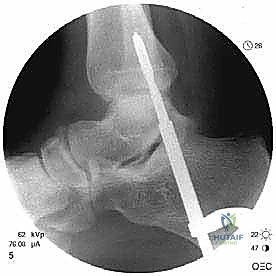

| Standard weight-bearing ankle radiographs (anteroposterior [AP], lateral, and mortise) define the bony ankle anatomy alignment. In cases of peroneal tendon subluxation, radiographs are usually negative. In a grade 3 injury, a “fleck” of bone can be seen off the posterior distal fibula and is considered pathognomonic of an SPR injury (FIG 3). | |||

| * FIG 3 • Fleck sign on a radiograph. The best view to see this on is the mortise view. | |||

| Routine ankle radiographs are essential to identify or rule out a rim fracture of the distal fibula, which occurs in 15% to 50% of all cases of peroneal subluxation.1 | |||